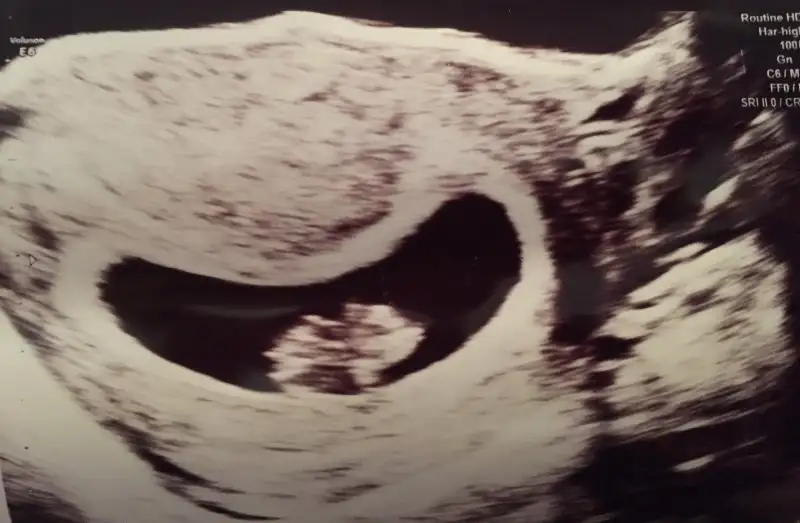

Kızlar banada bakıp tahmin yapabilirmisiz bugn çekildi 7hafta 1 günlük

Teşekkür ederimCnm bu teoriye gore erkek,bebegin keseDe

Erkeğe benziyor canim ..sen yinede 8. Hafta yada 9. Haftaya girince yeniden resim at. Tabi hakkinda hayirlisi onceKızlar banada bakıp tahmin yapabilirmisiz bugn çekildi 7hafta 1 günlük